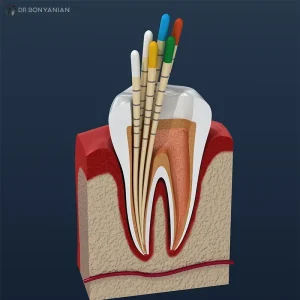

عصب کشی کردن دندان تنها نیمی از مسیر درمان دندان آسیب دیده است. نیمهی دیگر آن به زمان و شیوه ی پر کردن دندان بستگی دارد. این تصمیم ساده، سرنوشت دندان را تعیین میکند: باقی ماندن در دهان یا شکست درمان و نیاز به کشیدن دندان.

اهمیت پر کردن دندان بعد از عصب کشی

عصب کشی هرچند عفونت و التهاب موجود درون دندان را از بین میبرد، اما به دلیل برداشته شدن بخشهایی از بافت داخلی، مقاومت کلی دندان کاهش پیدا میکند و این دندان نسبت به قبل شکنندهتر میشود.

از طرفی اگر پر کردن دندان بیش از حد به تعویق بیفتد، فضای خالی ایجاد شده میتواند محل نفوذ دوباره ی میکروبها و باکتریها شود و همین موضوع احتمال عفونت مجدد و شکست کل درمان را بالا میبرد.

از سوی دیگر، دندانی که هنوز پر نشده باشد، هنگام جویدن غذا فشار زیادی را تحمل میکند و به دلیل نداشتن استحکام کافی در برابر این فشارها، بسیار آسیبپذیر خواهد بود و حتی ممکن است دچار ترک یا شکستگی کامل شود.

پس ترمیم یا پر کردن دندان بعد از عصب کشی، نقشی حیاتی در پیشگیری از ترک خوردن و شکستگی دندان ایفا میکند. زیرا این مرحله همان حفاظی است که دندان را برای ادامه عملکرد طبیعی و طولانی مدت آماده میسازد.